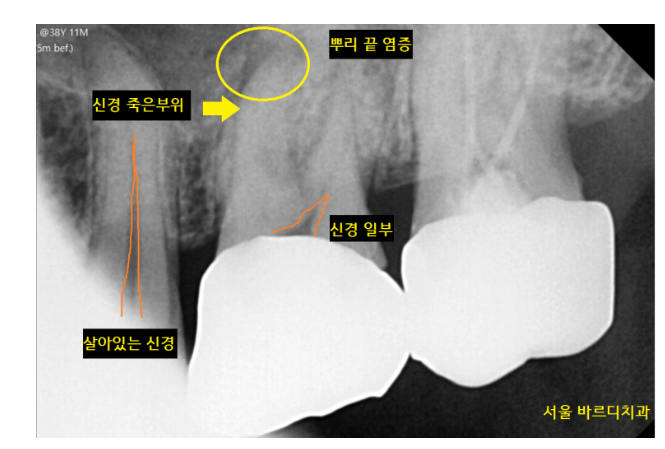

그렇지만 방치할 경우 뿌리 끝에 고름이 잡히고

열감, 통증, 얼굴 붓기 증상이 동반되기도합니다.

신경이 이미 괴사되어버리면

치료하기 더욱 까다로워지고요

231214 치아 신경이 죽으면 X RAY 상에서 확인됩니다